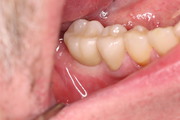

Socket + Implantation 3,5 Jahre Follow up

Nach Entfernung der Zähne 46 und 47, Augmentation DentOss fein, Adaptationsnähte, 6 Tage danach, Implantation nach 5 Monaten und ZE 45, 46 mit Zirkonkronen.Röntgenkontrolle nach einem Jahr und klinische Situation. 3,5 Jahre nach Socket.